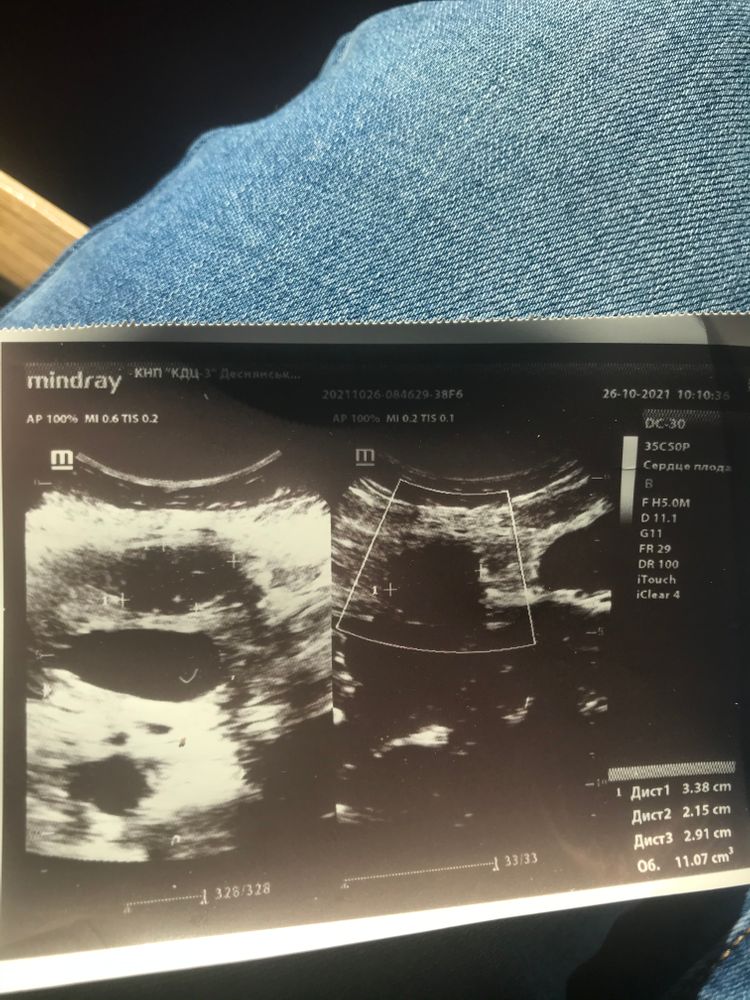

Девочки, привет.Ранее писала пост поповоду миомы, до беременности была миома примерно 2/1,5 см.Сегодня на узи врачь сказал что миома плоду не мешает и все прекрасно (по узи она на этот момент 3,3/2,1 см), пошла к своему врачу она годовой качает, я спрашиваю в чем дело, она говорит что на фото (как я поняла) миома близко около плода или около плаценты (миома субсерозная по передней стенке и плацента по передней)Прикрепляю фото, может у кого такое было, как все закончилось?!